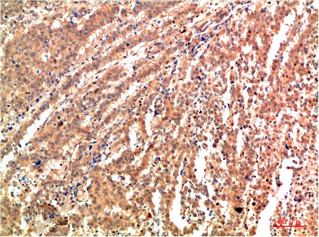

JNK2 Rabbit Polyclonal Antibody

WB, IHC, IF

WB 1:500-2000; IHC 1:50-300; IF 1:50-200